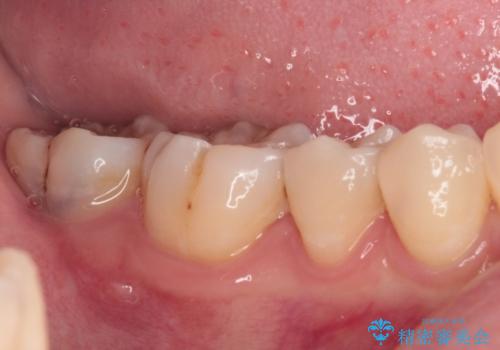

精度の高いセラミックインレーによる修復治療を行うこととしました。

処置を行った歯以外にもむし歯と思われる歯が多数ありますが、費用のかかる治療であれば、優先順位をつけて、処置を急ぐ歯から処置を進めて行きました。